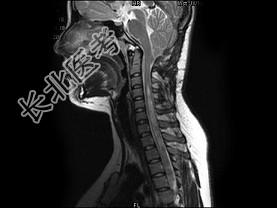

- 单项选择题女,16岁, 四肢活动不利半年,走路不稳2个月, MRI检查,最可能的诊断为 ( )

C、Chiari畸形(Ⅰ型)并脊髓空洞形成